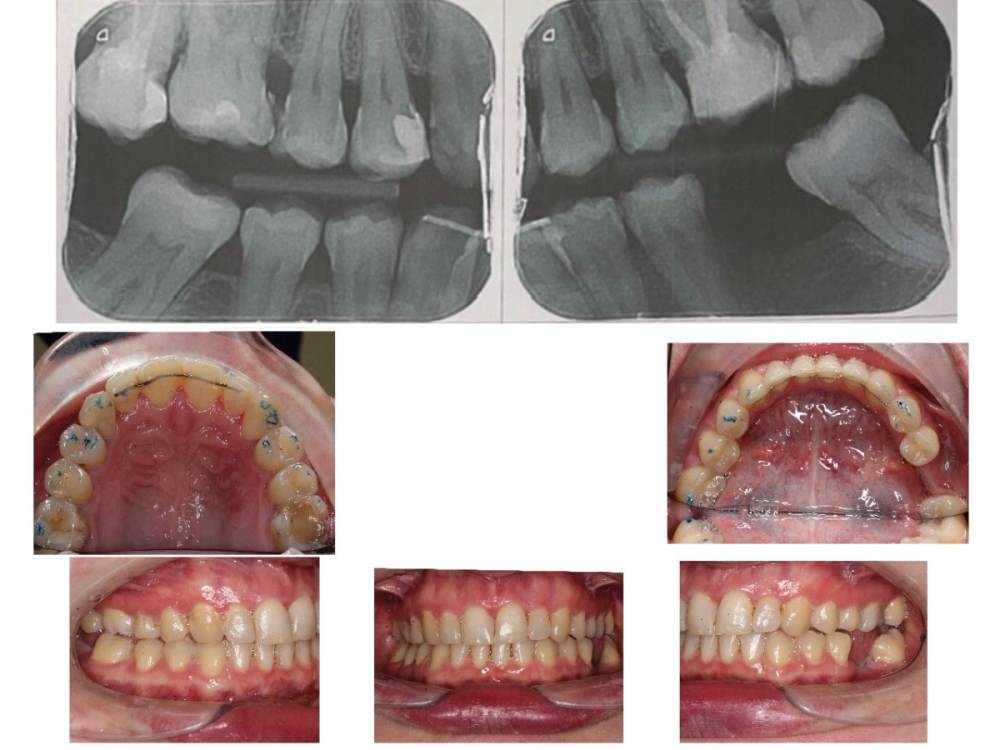

Здравствуйте, в стране проживания я прошла ортодонтическое лечение (3 года в брекетах). Меня не устраивает результат, но к сожалению все ортодонты тут с которыми я говорила не хотят ничего делать, тк их результат устраивает. У меня вопросы :

1. можно ли установить имплантанты внизу как 6 и 6 или 6 и 7

2. что делать с верхней семеркой ? Ее хотят удалить, не хотят ставить коронку.

3. что делать с окклюзией. Это действительно все нормально? Такой угол для 7го зуба это нормально? 2ая окклюзия с другой стороны это нормально?

4 стерся клык о брекет- как сделать улыбку снова симметричной ?

5 сколько продержатся зубы без лечения тут - на верхних зубах с 1й стороны кариес, нужны коронки на верхних 6 и 7 ( разные стороны)

какие способы решения проблемы существуют? Тк тут мне никто помочь не хочет, то я вижу выход только попробовать myobrace - вдруг он вернёт среднюю линию на место и сделает окклюзию лучше. как только станет проще путешествовать - ездить с маленьким ребёнком в россию, там мб поставить брекеты, коронки, имплантанты.

Какой порядок действий должен быть? Как все сделать быстрее и не потерять больше зубов?

тут мне говорят что сделать апрайтинг невозможно , как и передвинуть среднюю линию, и все нормально с зубами. Что мне вообще делать и как жить?